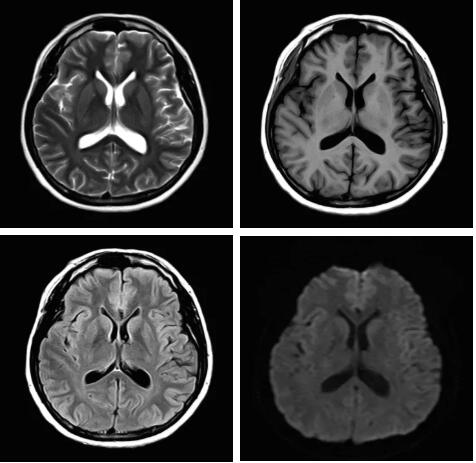

見(jiàn)所未見(jiàn) 微小腫瘤無(wú)處遁藏——

“螢火蟲(chóng)”成像技術(shù) 顱內腫瘤微小病灶檢出新發(fā)現

此技術(shù)主要用于神經(jīng)系統惡性腫瘤,以及其他腫瘤腦轉移瘤篩查。傳統情況下做腫瘤腦轉移篩查,很容易漏掉5mm以下小病灶,臨床發(fā)現后干預治療比較晚,要實(shí)現2mm高空間分辨率和超薄層全腦掃描在保證信噪比的情況下需要很長(cháng)時(shí)間大概十多分鐘,而且薄層增強序列顱內血管呈高亮信號,會(huì )干擾顱內小病灶的觀(guān)察,血管和小病灶區分困難。佳能”螢火蟲(chóng)”成像技術(shù)既可以實(shí)現高空間分辨率和超薄層(最薄可實(shí)現0.2mm)全腦掃描,掃描時(shí)間短,2-3分鐘即可實(shí)現全腦3D掃描,同時(shí)避免了血管高亮信號的干擾,對顱內原發(fā)或繼發(fā)的微小腫瘤檢查有重大意義。“螢火蟲(chóng)”成像技術(shù)具有磁敏感效應,對于亞急性血敏感敏感,可以區分出血和強化的腫瘤。